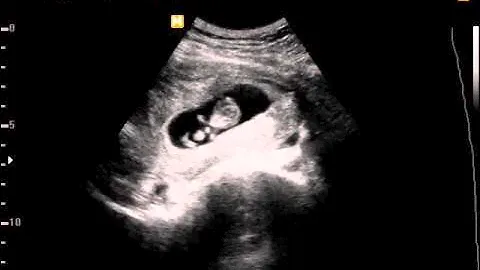

🥹ГОТОВЬТЕ ПЛАТОЧКИ! | Первое узи, как узнали пол, услышали сердцебиение, первые толчки.. ❤️